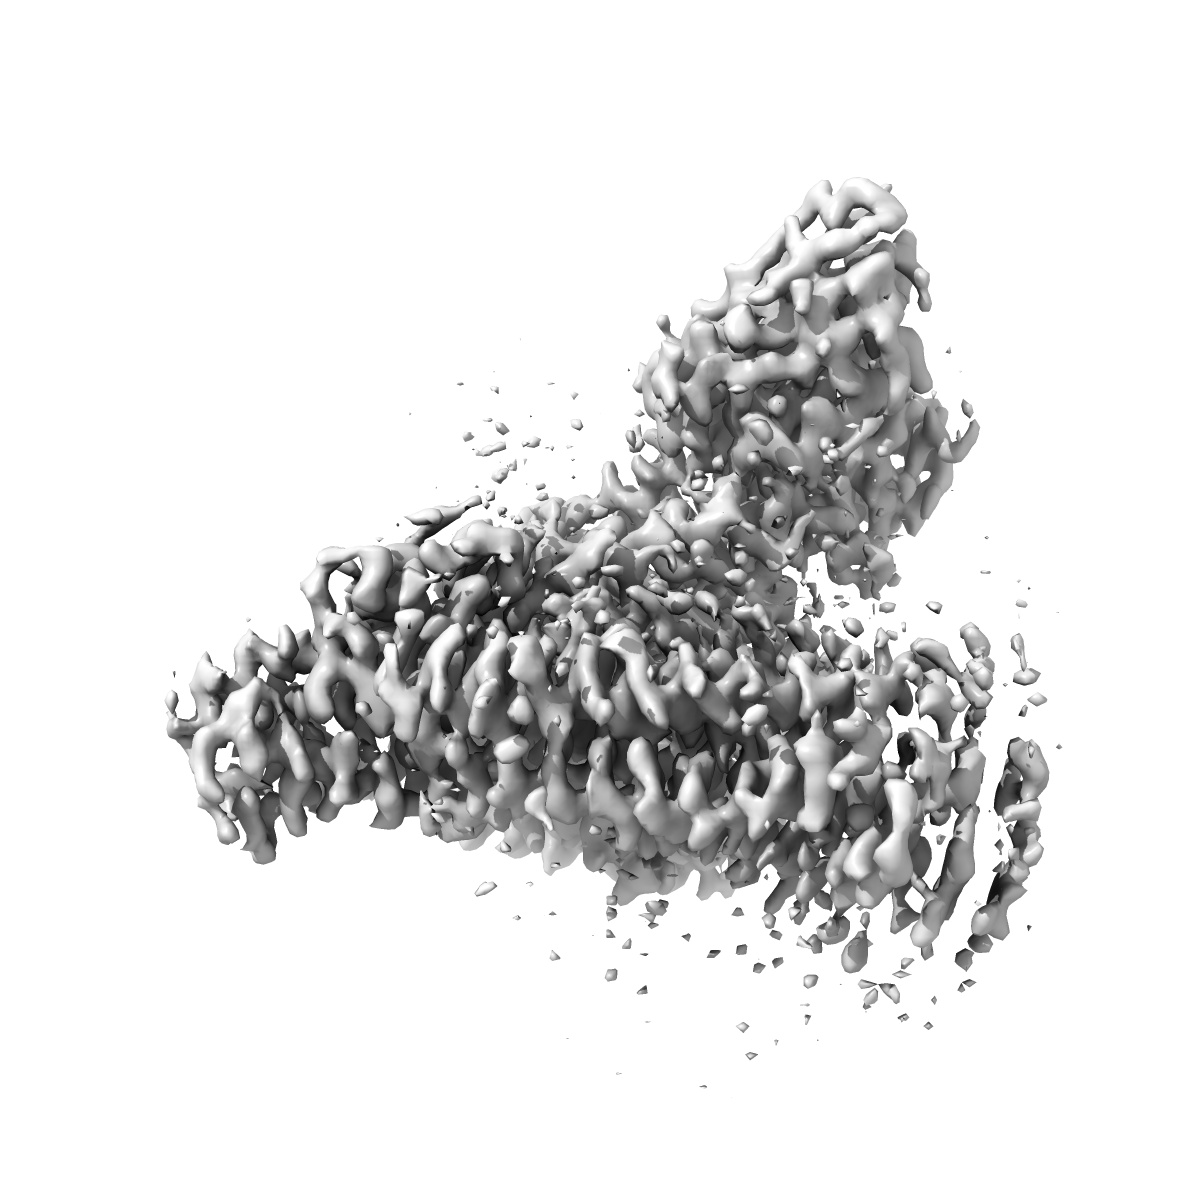

EMD-47992

Cannabinoid receptor 1-Gi complex with novel ligand

Composite mapSingle-particle

3.2 Å

Sample: Signaling complex of the cannabinoid receptor 1 bound to Gi

Virtual library docking for cannabinoid-1 receptor agonists with reduced side effects.

(2025) Nat Commun , 16 , 2237 - 2237